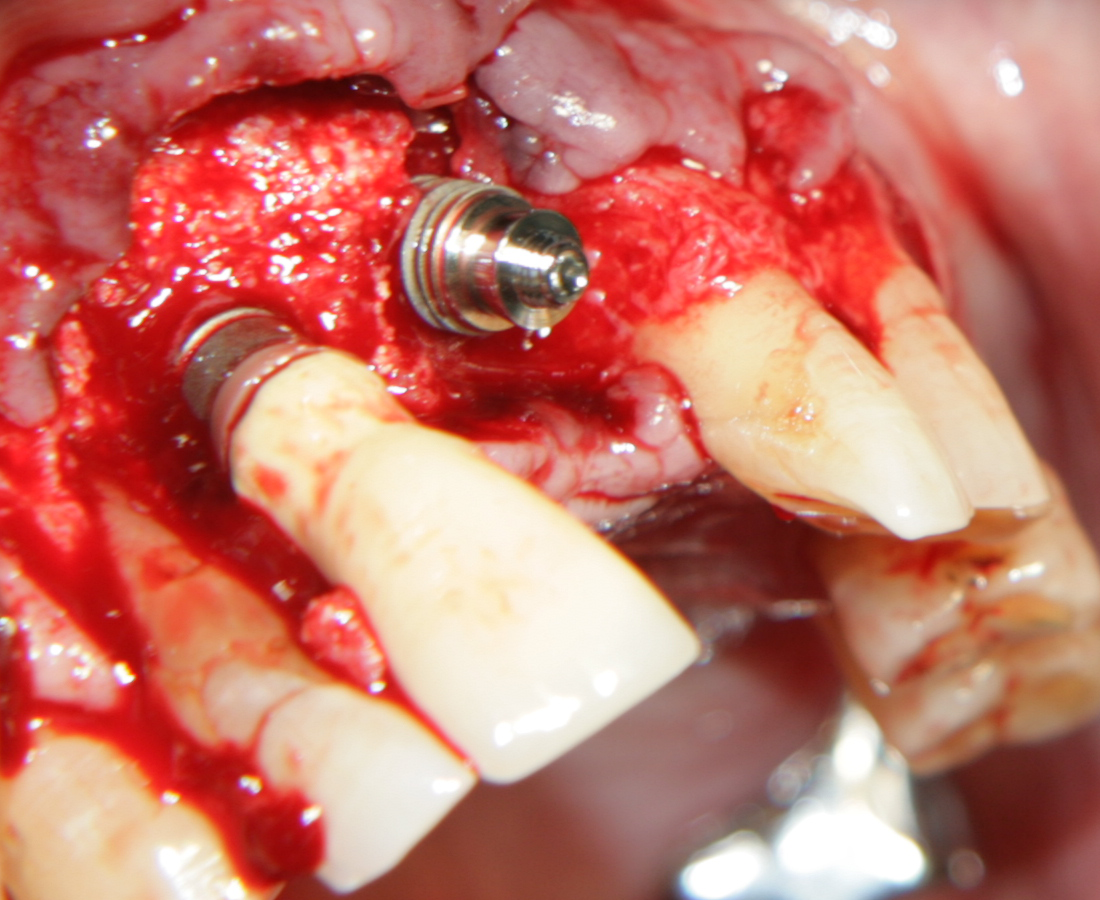

Tent screw - винтове за

фиксиране на титановата мрежа

Около винтовете се поставя костозаместител, добре е да се размеси с

автогенна кост

Титанова мембрана

PRF